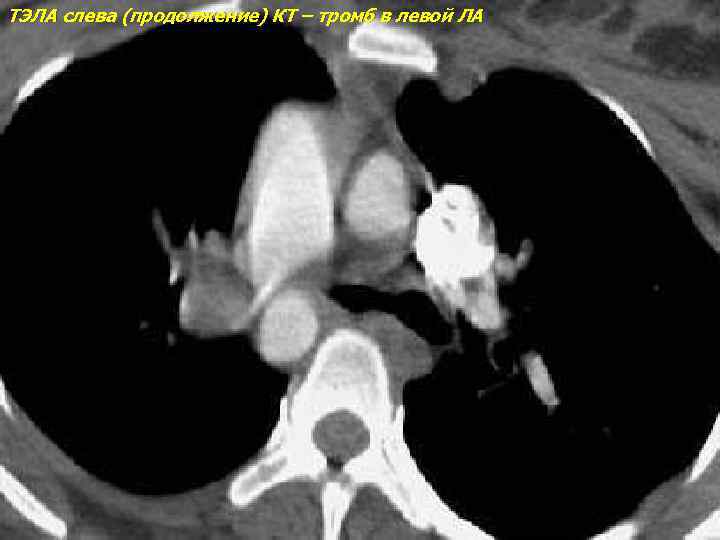

ТЭЛА слева (продолжение) КТ – тромб в левой ЛА